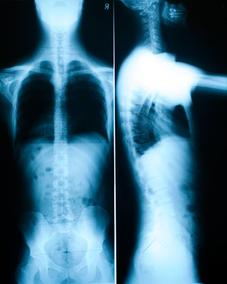

X-Ray: AP and lateral full spine STANDING x-rays are taken of each and every patient                                                                      (young children and pregnant women are not x-rayed unless unusual circumstances                                                                      occur). This x-ray will determine the health of a person’s spine. The standing or                                                                                “weight bearing” position insures perfect view of the patient’s posture in its natural                                                                        state. It also gives the Doctor a “blueprint” of a person’s spine showing misaligned                                                                          vertebra and pelvic bones and giving the Doctor a look at the discs (the ligamentous                                                                      cushions between the vertebrae.) This x-ray will help the Doctor determine the                                                                                precise angle and direction that each individual subluxation will need to be                                                                                      corrected.